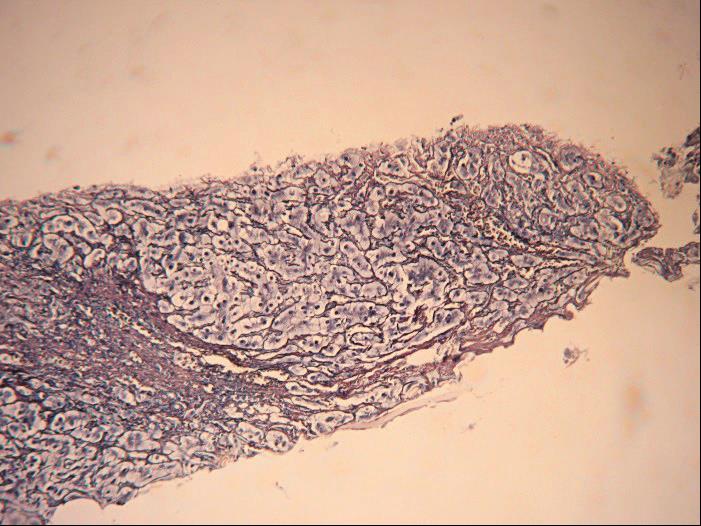

图4-3-3 酒精性肝病

酒精性肝纤维化,广泛窦周纤维化伴纤维间隔形成,部分小叶结构紊乱(网状纤维染色)